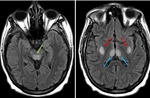

Sáng 11/5, bệnh nhân Nguyễn Đức (36 tuổi), người em trong cặp song sinh Việt- Đức, đã lên bàn mổ tại Bệnh viện Bình Dân để các bác sĩ thực hiện phẫu thuật nối lại niệu quản vào bàng quang.

Trước đó, tại bệnh viện Bình Dân, Nguyễn Đức đã được mổ mở thận ra da bằng ống thông nhỏ để điều trị thận ứ nước nhiễm trùng trên quả thận độc nhất.

Theo PGS.TS.BS.Nguyễn Phúc Cẩm Hoàng, Phó giám đốc bệnh viện Bình Dân, đây vốn là một ca phẫu thuật phức tạp, quyết định phẫu thuật cắm lại niệu quản vào bàng quang cho bệnh nhân Nguyễn Đức đã được Hội đồng Khoa học Công nghệ của bệnh viện cân nhắc nhiều lần. Phẫu thuật này nhằm khắc phục tình trạng hẹp niệu quản vốn đã gây tình trạng nhiễm trùng hệ niệu tái phát nhiều lần ở người bệnh. Dự tính, ca phẫu thuật sẽ diễn ra trong khoảng 3 giờ.

"Do tình trạng dị tật bẩm sinh của hệ tiết niệu diễn tiến phức tạp theo thời gian, nếu không được phẫu thuật tạo hình, Nguyễn Đức sẽ phải đeo ống thông dẫn lưu nước tiểu suốt đời và nguy cơ biến chứng trên chức năng của thận", bác sĩ Nguyễn Phúc Cẩm Hoàng cho biết thêm.